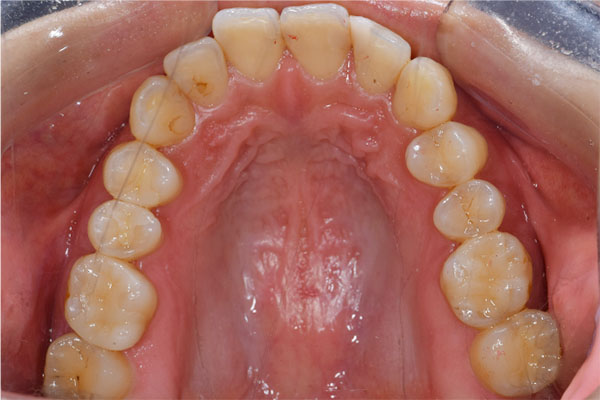

【担当医師所見】

治療前、左上大臼歯部は咬合面(咬む面)も無くカリエス(虫歯)も大きいものでした。

治療後、理想的な位置にインプラントが埋入され正しく咬むことができるようになりました。